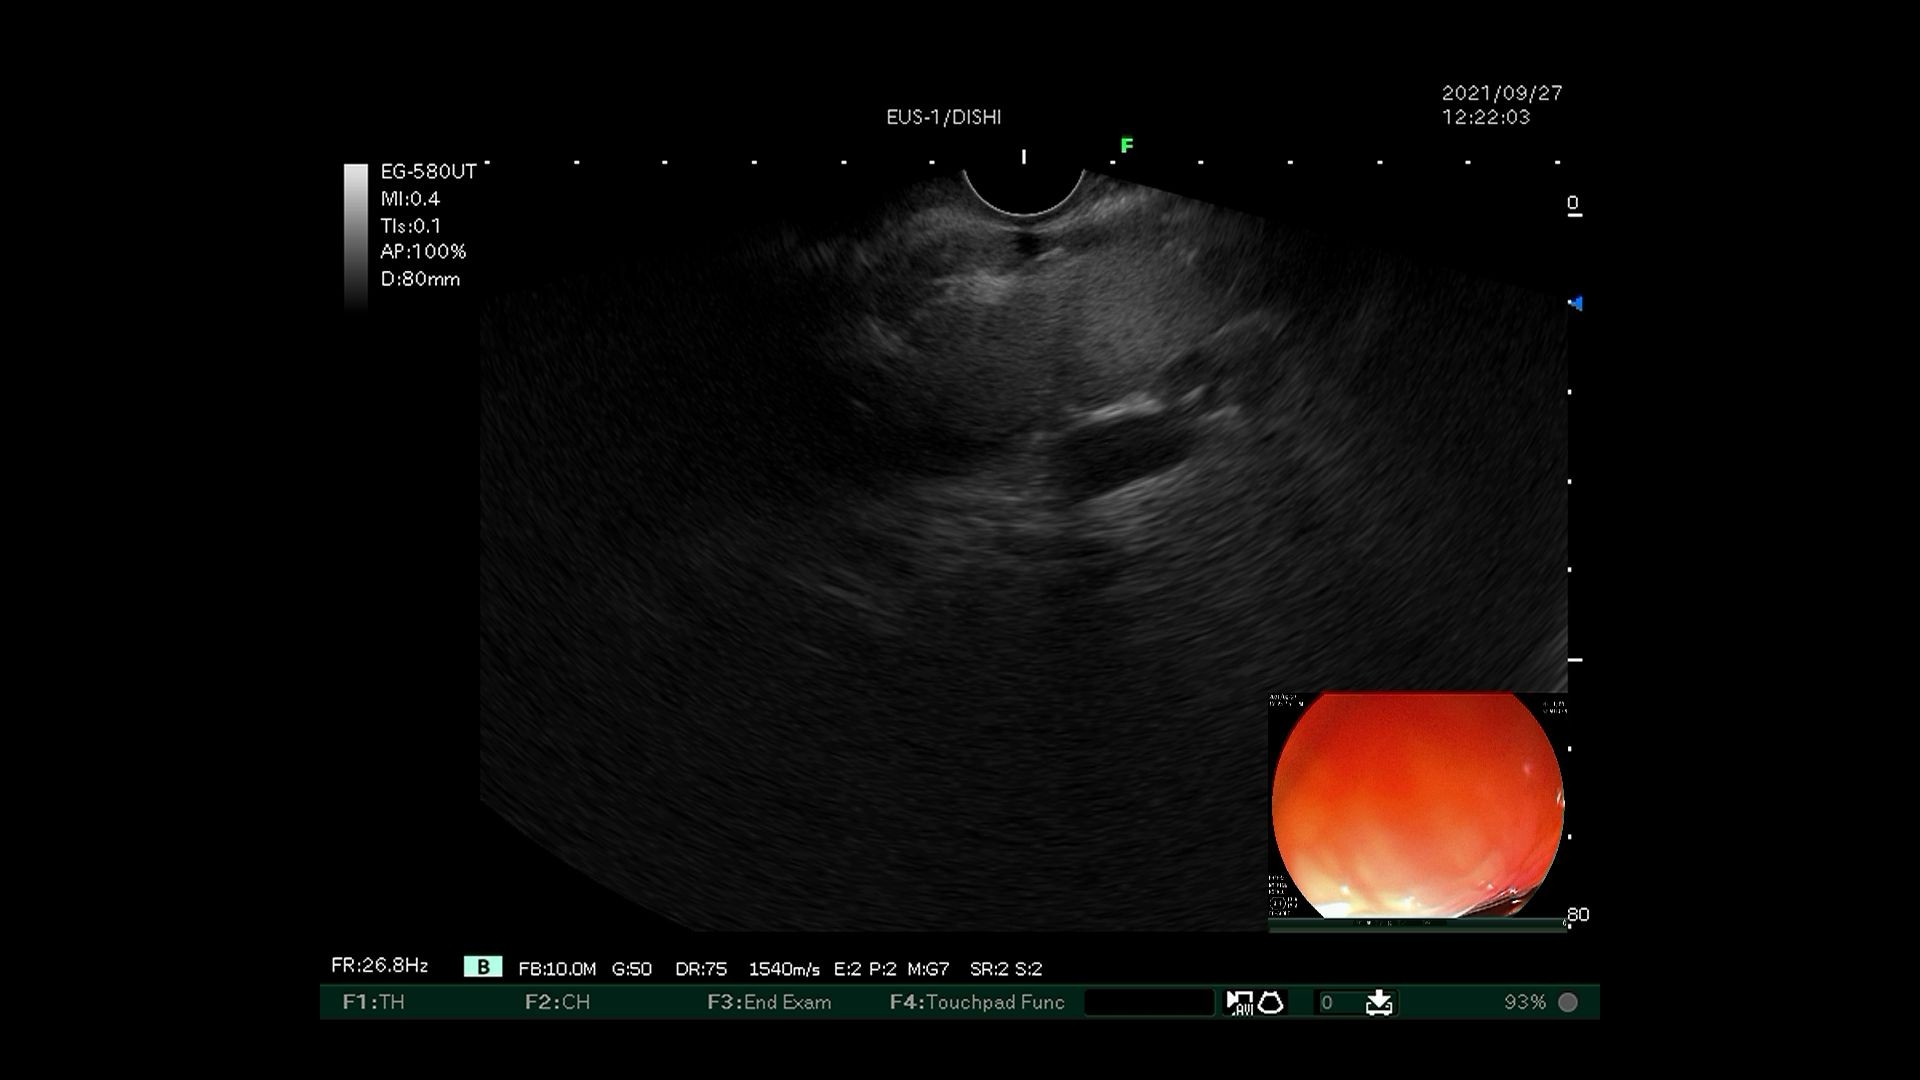

6)超声内镜确认曲张静脉血流信号消失。